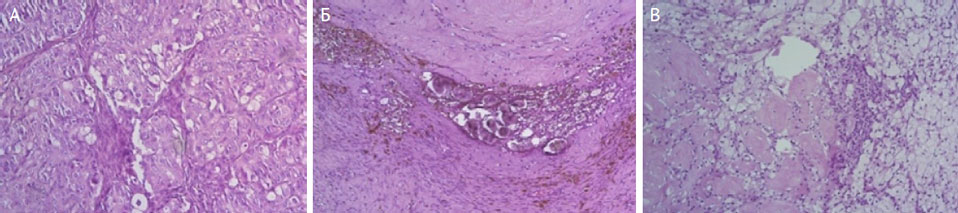

Ответ опухоли на лечение проиллюстрирован на рис. 3.

Рис. 3. Иллюстрации ответа опухоли на лечение: A — CRS1 (в срезах сплошь опухолевая ткань); Б — CRS2 (в срезах легко выявляется жизнеспособная опухоль, но также выражены и изменения, указывающие на регресс опухоли); В — CRS3 (опухолевые клетки не выявляются совсем, но присутствуют стромальные изменения, ассоциированные с регрессом опухоли)